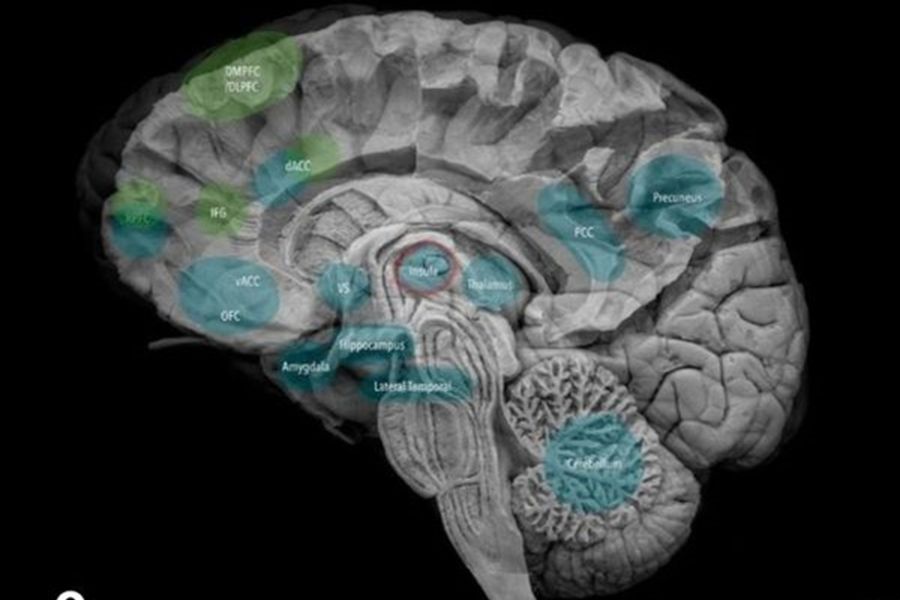

Neurosonografía fetal : Desde las 20 a 41 semanas

Neurosonografía fetal: Desde las 20 a 41 semanas